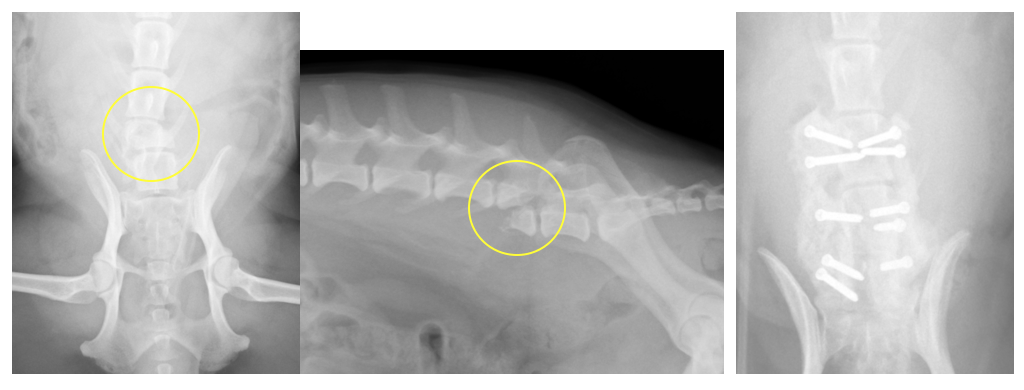

犬の椎体骨折・椎体不安定に対する椎体固定術

交通事故などで背骨が折れてしまったり、椎間板の問題でズレが生じ不安定性がある場合、背骨の中を通る脊髄に障害をきたし、歩行異常や麻痺などの症状が出ます。

椎体骨折や椎体不安定の場合、椎体を何らかの方法で固定し、元の位置に安定化させる必要があります。

小型犬〜中型犬で安全性が高く強固な固定は、折れている(ずれている)背骨とその前後の椎体にスクリューを打ち込み、打ち込んだスクリューを骨セメント(PMMA)という物質で固める方法です。

他にもプレートやピンを使用する方法もあります。

手術自体は難易度が高いのですが、Cアームという透視装置を導入したことで以前ほどの危険性はなくなりました。

交通事故で椎体骨折した症例です。左右からスクリューを打ち込み、そのスクリューを骨セメントで固定することで、背骨のグラつきをなくしています。

椎間板の問題で椎体にずれが生じた症例です。骨折ほど大きなズレではないため、片側からスクリューを打ち込み、それを骨セメントで固定しています。この症例は椎間板ヘルニアの手術で減圧術(ヘミラミネクトミー)も同時に行いました。